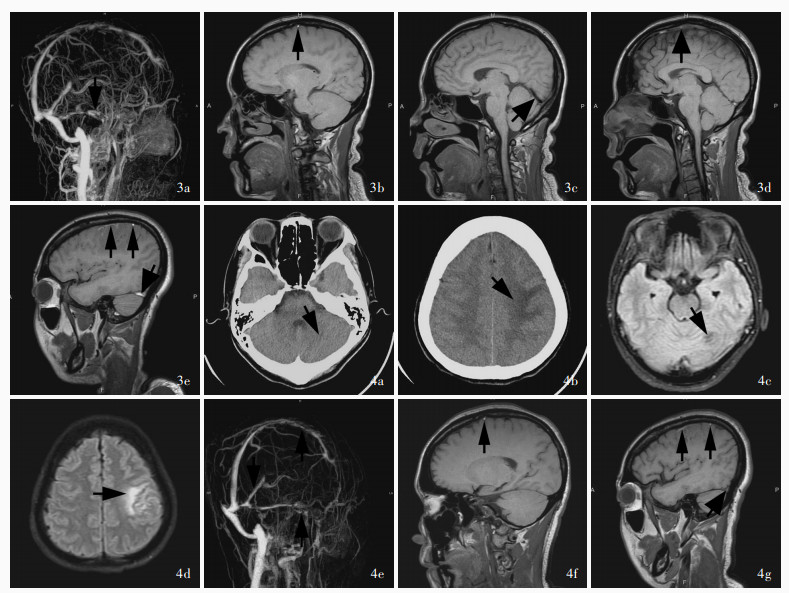

Hu SY , Zhang KY , Gu YQ , Li JK , Zhou C , Ji XM , Duan JG . Exploration of glucocorticoid combined with anticoagulation in acute/subacute severe cerebral venous thrombosis. Shou Du Yi Ke Da Xue Xue Bao, 2023, 44: 280- 288.

胡舒缘, 张开元, 谷亚钦, 李京凯, 周陈, 吉训明, 段建钢. 糖皮质激素联合抗凝在急性/亚急性重症颅内静脉血栓治疗中的探索. 首都医科大学学报, 2023, 44: 280- 288.

Hu S, Gu Y, Zhao T, Zhang K, Li J, Zhou C, Song H, Liu Z, Ji X, Duan J. Steroids combined with anticoagulant in acute/subacute severe cerebral venous thrombosis[J]. Chin Med J (Engl), 2025. [Epub ahead of print]